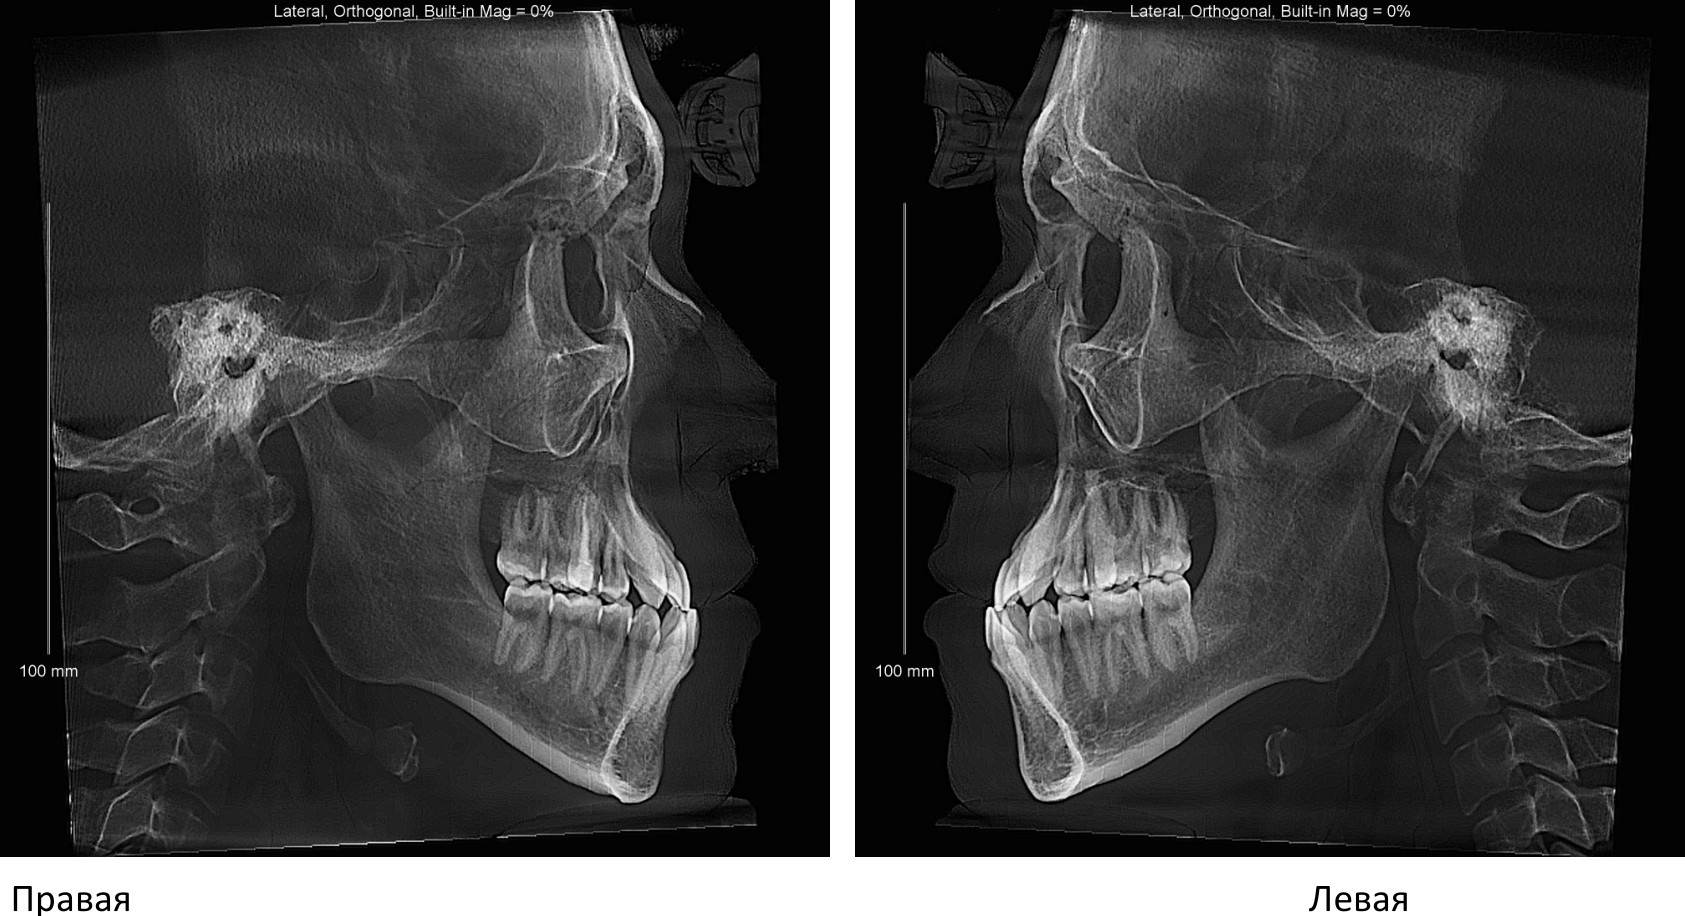

призвыаю всех пиливших челюсти по квоте в тред похоже, мой путь только начинается, чё раскажете инте